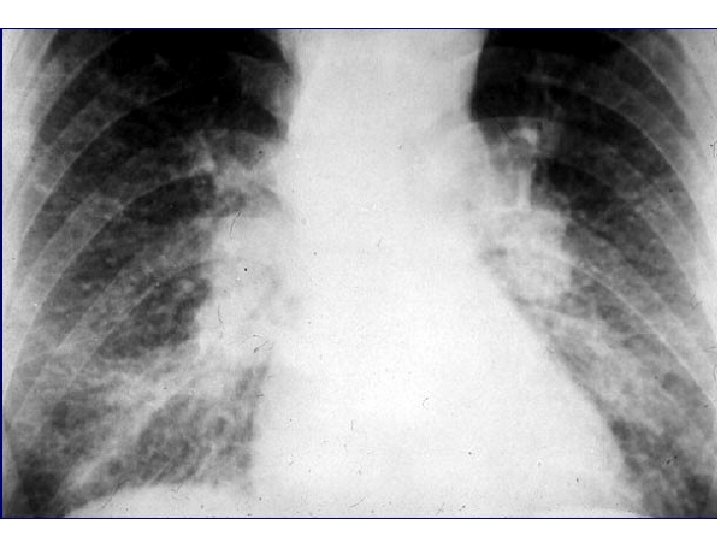

E- Miliaire des granulomatoses : 1 - Granulomatose immuno-allergique : • Poumon de fermier. • Maladie des éleveurs d’oiseaux. • Maladie des championistes … 2 - Granulomatose d’étiologie inconnue : • Sarcoïdose : prédomine à la région hilaire avec ou sans ADP. • Histiocytose X.

Sarcoïdose Le Stade II